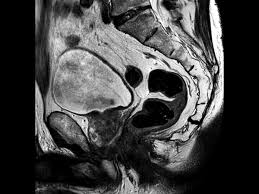

Sequential axial images from above the level of the base to the level of the apex of the prostate.

Anatomical changes during physiological voiding in men. The probe is angled from one side. The important role of magnetic resonance imaging (mri) in the anatomic evaluation, detection, and staging of prostate cancer is well established. Axial t1wi of pelvis 2.